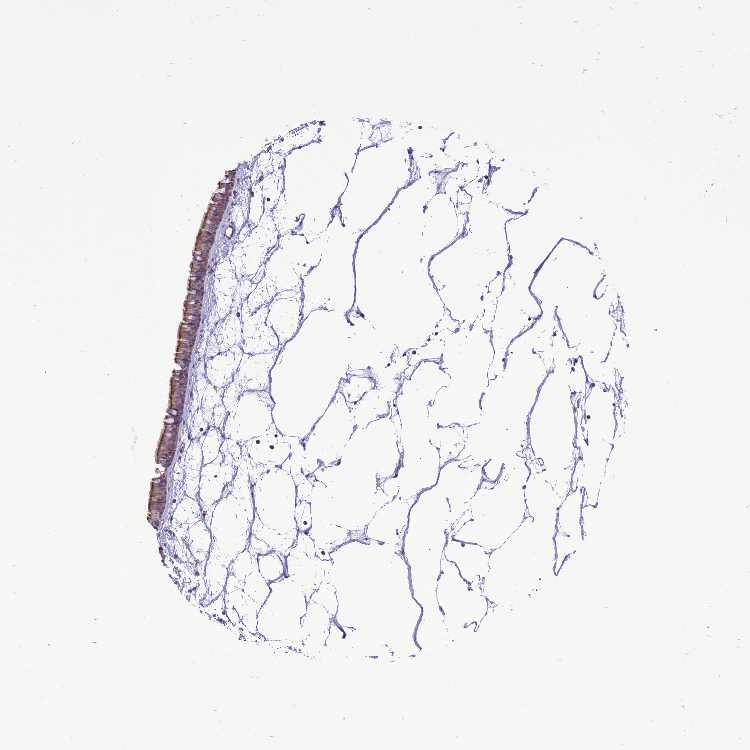

TISSUE PRIMARY DATA NASOPHARYNX Show tissue menu

Nasopharynx

NASOPHARYNX - Antibody stainingi

Antibody staining in the annotated cell types in the current human tissue is reported as not detected, low, medium, or high, based on conventional immunohistochemistry profiling in selected tissues. This score is based on the combination of the staining intensity and fraction of stained cells.

Each image is clickable and will lead to virtual microscopy that enables deeper exploration of all samples and also displays staining intensity scores, fraction scores and subcellular localization as well as patient and tissue information for each sample.

Antibody HPA043567Antibody HPA050340

Respiratory epithelial cells MediumLow